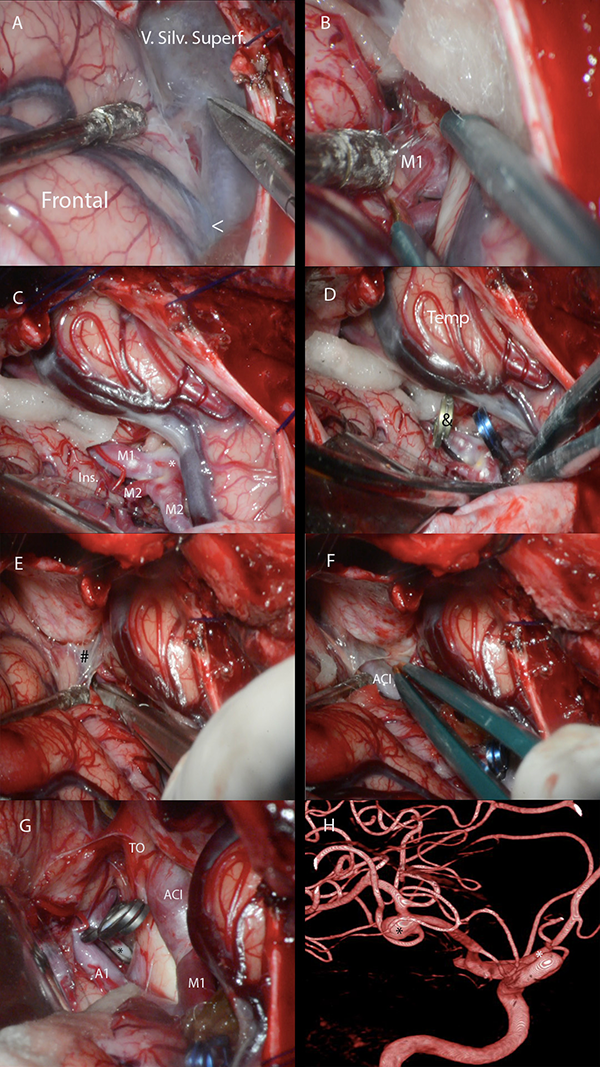

Figura 10: A-G. Fotos quirúrgicas de disección de la FS para clipado de aneurismas de bifurcación de ACM derecha y de arteria comunicante anterior. La disección comienza 10-15 mm proximal a la confluencia venosa silviana. El límite medial de la cisterna silviana es la membrana silviana proximal que se adhiere superiormente a la estría olfatoria lateral e, inferiormente, a la incisura rinal. Su apertura permite el acceso a la cisterna carotídea. V. Silv. Superf: vena silviana superficial; Ins: ínsula; Temp: lóbulo temporal; TO: tracto óptico; ACI: arteria carótida interna; <: confluencia venosa silviana; *: aneurisma; &: clip transitorio; #: membrana silviana proximal. H. Angiografía digital carótida derecha correspondiente. *: aneurisma.

Durante la cirugía, con la membrana aracnoidea intacta, no es fácil identificar las estructuras anatómicas como se hace en los especímenes cadavéricos disecados. Es por esto que los cirujanos pueden usar como punto de referencia para localizar al punto silviano anterior al área más prominente y anterior del giro frontal inferior que se continúa, luego de un borde agudo, con la superficie basal del cerebro. Esta área prominente es la pars orbitalis (Figura 9A). Los giros frontoorbitarios y la superficie basal de la FS solamente son expuestos luego de que el ala menor del esfenoides es removida. Unos pocos milímetros posteriores a esta área, uno puede asumir con seguridad que se localiza la pars triangularis. Más aún, la punta de la pars triangularis suele apuntar a un ensanchamiento prominente de la FS: el punto silviano anterior (Figura 3). También, dado que el punto silviano anterior se localiza donde la fisura silviana pasa de la superficie basal a la lateral, ubicar el sitio donde la fisura cambia de sentido, es otra forma de encontrar este punto microquirúrgico. Finalmente, cuando la parte superficial de la FS está deformada porque el opérculo frontal indenta al temporal, o viceversa, o, cuando la membrana aracnoidea es particularmente opaca, el neurocirujano debe localizar la unión de la vena superficial temporal con la frontal. Este punto es nombrado en la literatura como “confluencia venosa silviana”. El punto silviano anterior se localiza unos milímetros proximales a la confluencia venosa silviana (Figura 8B y 10A).

Los autores comienzan a disecar la FS en el punto silviano anterior debido a que allí se encuentra una “subcisterna” aracnoidea natural generada por una retracción espontánea de la punta de la pars triangularis (Figura 5A). Además, la orientación oblicua inferior en el plano coronal del plano polar del lóbulo temporal (Figura 11C y D), así como también, su dirección lateromedial, contribuyen a la amplificación del espacio subaracnoideo en este punto microquirúrgico esencial. Para acceder a las cisternas aracnoideas basales, la fisura es disecada desde la superficie lateral a la basal. Solo cuando es necesario, las cisternas carotídeas, interpeduncular y quiasmática son abiertas previamente. Esto es útil, por ejemplo, cuando hay hipertensión intracraneal debido a la ruptura de un aneurisma, y se precisa bajar la tensión para realizar la disección. Debe ser tenido en cuenta que para liberar una cantidad considerable de líquido cefalorraquídeo (LCR) con este propósito, es recomendable abrir la cisterna carotídea, así como también la interpeduncular, a través de la disección de la membrana de Liliequist. La cisterna carotídea es una cisterna relativamente pequeña, que, si es abierta aisladamente, solo liberará una pequeña cantidad de LCR.

Con una hoja de bisturí N 11, y retrayendo gentilmente el opérculo con una cánula de aspiración delicada con mínima presión de succión, se incide la membrana aracnoidea, preferiblemente en el lado frontal de la vena silviana superficial (Figura 10A). Consecuentemente, de necesitarse retraer el lóbulo frontal con una espátula, las venas serán mejor preservadas. El cirujano debe siempre intentar preservar el drenaje venoso. Sin embargo, solo si es imperativo las venas silvianas pueden ser coaguladas. No se debe usar sistemáticamente retractores estáticos. El uso de pequeños algodones permite una suave separación de las estructuras cerebrales con mínima presión (Figura 10B). Más aún, cuanto más se expone al lóbulo temporal en la craneotomía, más simple será abrir la fisura. Así también, cuanto más se drilla la pared lateral y techo de la órbita y el ala menor del esfenoides, será necesaria menor retracción cerebral y se conseguirá más exposición de la parte basal. Continuando desde el punto de inicio, las membranas aracnoideas son incididas con una hoja de bisturí o con microtijeras.

El primer compartimiento silviano que es disecado desde el punto silviano anterior es el compartimiento opercular anterior. La mayoría de las FS tienen un compartimiento opercular anterior curvilíneo irregular. Esto se debe frecuentemente a una pars orbitalis prominente que indenta y comprime al plano temporal. Una vez que este compartimiento es disecado, si el cirujano continúa proximalmente y en profundidad por la fisura, se accede al compartimiento esfenoidal. Con una cánula de aspiración delicada con mínima presión de succión, pinzas bipolares bayonetada y microtijeras, se progresa la disección.

Las ramas y segmentos de la ACM no siempre se identifican con claridad. En función de poder hacerlo, es útil disecar los vasos arteriales desde distal a proximal hasta que la bifurcación carotídea es identificada, y luego seguir a la ACM en dirección opuesta, de proximal a distal. M1 debe ser disecada por su cara anterior. Esto es porque las arterias lenticuloestriadas usualmente nacen de su cara superior o posterosuperior (Figura 1C,10C, 10D).

El límite medial de la cisterna silviana es la membrana silviana proximal que tiene un color blanco perlado y es opaca (Figura 8B y 10E). Se accede a la cisterna carotídea cuando esta membrana es abierta (Figura 10F). La bifurcación carotídea y los segmentos proximales de M1, A1 y sus ramas supraclinoideas, se ubican en la cisterna carotídea (Figura 1D y 10G). Esta cisterna se relaciona inferiormente con el segmento anterior del uncus y superiormente con el trígono olfatorio y el giro recto. La cisterna carotídea es un punto de encrucijada de las cisternas basales. Desde ella se puede alcanzar al tercer ventrículo a través de la lámina terminalis, a la cisterna carotídea contralateral, e incluso a la fosa posterior, a través de la apertura de la membrana de Liliequist, hacia la cisterna interpeduncular.

En este punto, es recomendable trabajar por la cara lateral de la carótida, en el espacio carotido-oculomotor. El espacio óptico-carotídeo, en la cara medial de la arteria carótida interna (ACI), tiene mayor número de arterias perforantes. Las arterias perforantes que corren paralelas a la ACI, se dirigen a la SPA. En cambio, las que irrigan al infundíbulo y al quiasma óptico, tales como la arteria hipofisaria superior, tienen un curso perpendicular a la ACI.

Si la superficie lateral de la FS necesita ser abierta, la disección continua distalmente. La técnica microquirúrgica es la misma que la descripta. El limen insular y la bifurcación de la ACM sirven como un punto de referencia confiable para comenzar a disecar al lóbulo insular, de anterior a posterior. El limen insular es un área donde se pueden encontrar muchos vasos arteriales. No solo los troncos superior e inferior de M2 se localizan aquí, sino también, las ramas corticales tempranas tienen su curso. Los opérculos son separados utilizando presión suave con la pinza bipolar y la cánula de aspiración delicada, siempre con la ayuda de algodones pequeños y, también, de microtijeras. A medida que los opérculos son disecados, se puede introducir algodones para gradualmente abrir el compartimiento operculoinsular lateral sin gran presión, hasta que toda la extensión de la fisura es disecada.